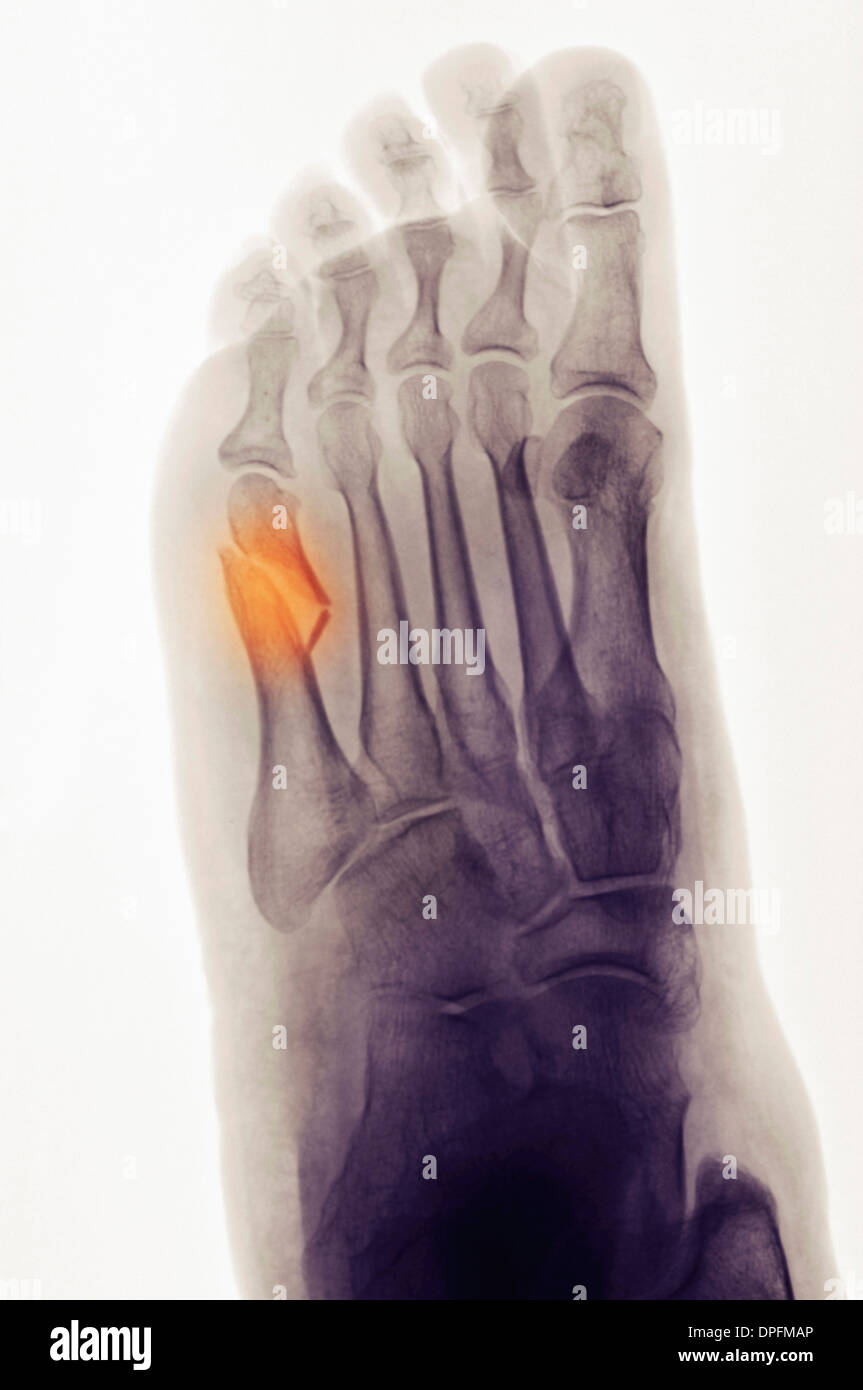

From www.alamy.es

Radiografía del pie que muestra una fractura del quinto metatarso Quinto Metatarsiano Fractura El correcto tratamiento conseguirá una recuperación completa. This activity describes the evaluation and. The proximal 5 th metatarsal is the site of a number of fractures. Fracturas de la base del quinto metatarsiano. 5th metatarsal base fractures are common traumatic fractures among athletic populations that are notorious for nonunion due to tenuous blood supply. Su estructura anatómica se divide en:. Quinto Metatarsiano Fractura.